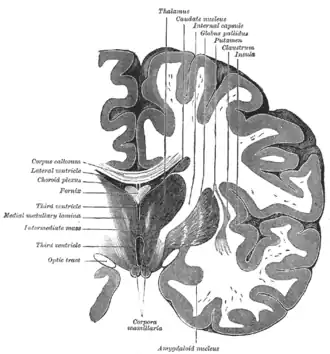

![]() | ||||

Coronale doorsnede van het brein (putamen is bovenaan gelabeld). | ||||